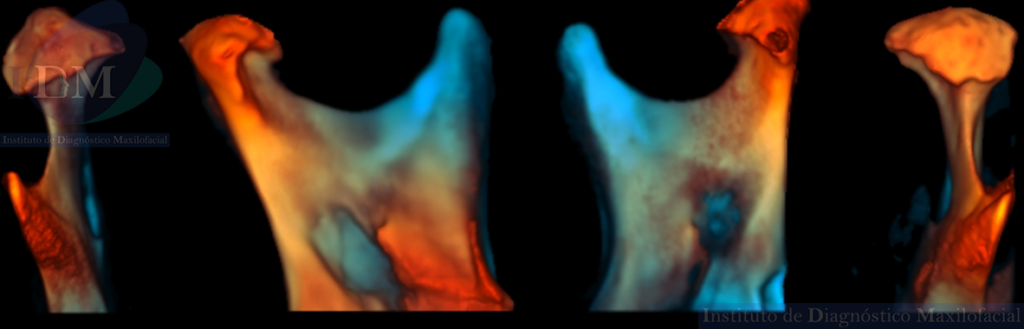

RECONSTRUCCIÓN 3D

- Trastorno degenerativo de ATM (Osteoartritis).

Con la introducción de la tomografía computarizada de haz cónico, se ha mejorado significativamente la visualización de los cambios tisulares asociados con la osteoartritis de la articulación temporomandibular (ATM). Los hallazgos típicos incluyen aplanamiento óseo, formación de osteofitos, esclerosis, erosión y la presencia de quistes óseos subcondrales. La degeneración del cóndilo de la ATM puede provocar maloclusión y deformidades faciales esqueléticas, como retrognatismo, mordida abierta anterior y asimetría facial (1,2).